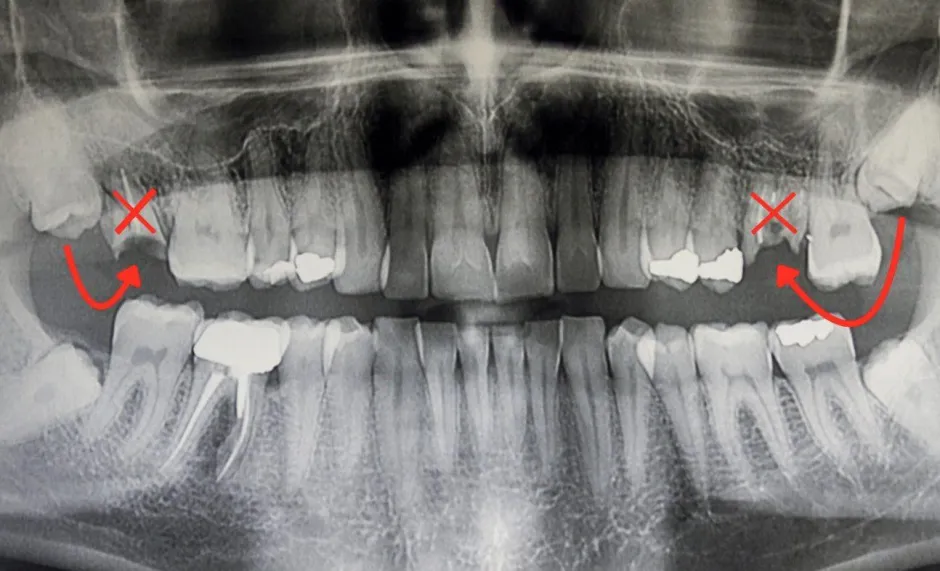

Ein typischer Fall fĂĽr eine Zahntransplantation ist der Verlust des ersten Stockzahns durch Karies oder Unfall bei Jugendlichen bis 23 Jahren. Hier kann der noch unberĂĽhrte Weisheitszahn, der friedlich im Kieferknochen schlummert, als natĂĽrlicher Zahnersatz dienen.